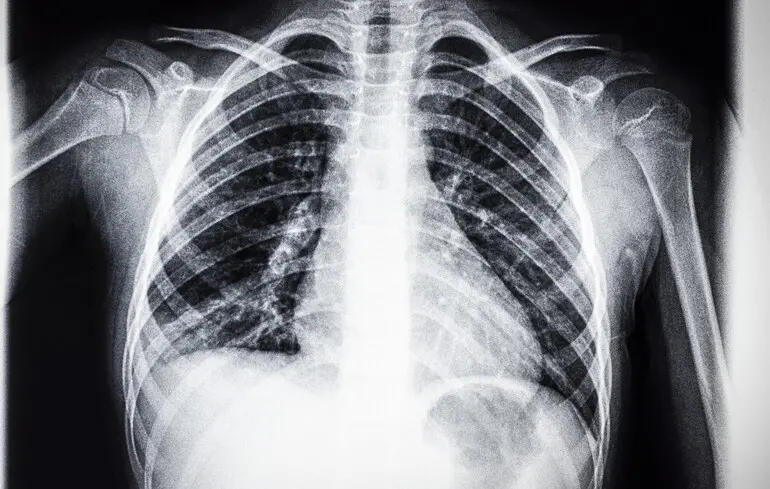

Национальное научное агентство Австралии CSIRO первым в мире разработало программу машинного обучения, чтобы специализировать искусственный интеллект на чтении рентгена грудной клетки. Натренированный таким образом ИИ оказался очень полезным при диагностике, сообщает Medical Xpress.

Для специализации ИИ на чтении рентгенов медицинские инженеры CSIRO создали базу данных из 46 000 анамнезов реальных пациентов, предоставленных больницами США. Также в большую языковую модель загрузили информацию обо всех существующих стандартах и требованиях к чтению радиологических отчетов.

Проверка на практике показала, что искусственный интеллект на 17% лучше ставит диагнозы пациентам, чем это делали профессиональные рентгенологи. Профессия сейчас переживает во всем мире нехватку кадров, поэтому технология может решить эту проблему и помочь улучшить работу многим медицинским учреждениям.

Это не впервые ИИ используют для чтения рентгеновских снимков. Но австралийская программа дает возможность научить искусственный интеллект полноценно использовать анамнез пациентов, а не только пленку.